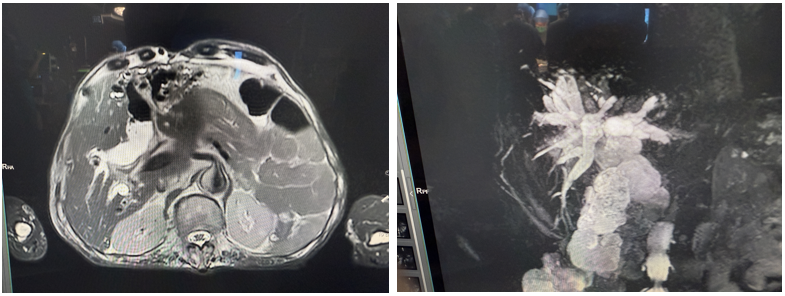

入院后,普外科付必莽教授团队接诊,根据蒋大爷的病史及辅助检查等情况,进一步完善检查后确诊"先天性胆管扩张症 4 型并节段性狭窄+肝内外胆管多发结石+胆囊残株结石",手术是唯一治疗方法。

为全力救治,普外科团队与全院 MDT 讨论后认为:蒋大爷的结石问题复杂,而且多发肺大泡并明显肺气肿,心功能也较差,射血分数仅 5 1 % 和 2 6%。如果要手术治疗,"解剖性左半肝切除+胆囊残株及结石切除+右肝胆管探查结石取出+胆肠吻合术"是唯一方案。

该病例再次提醒我们,准确诊断是制定合理手术方案的基础,而手术成功的关键:过硬的技术+合理手术方案+精准操作+围手术期精细管理,缺一不可!例如蒋大爷真正的病根(因)是胆管多发的扩张与狭窄,而结石只是"果",我们的治疗必须去"因"才可能彻底解决问题。但之前的所有治疗均是围绕"果",蒋大爷也就必然要持续忍受肝胆管结石的折磨!